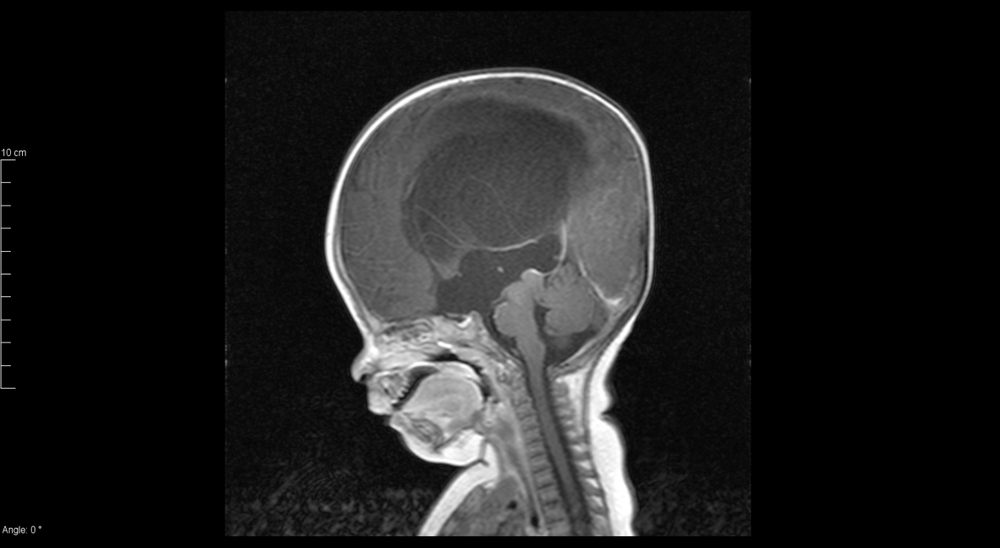

លោកជំទាវវេជ្ជបណ្ឌិត គ្រុយ លាងស៊ីម ទីប្រឹក្សាផ្នែកសម្ភព នៃមន្ទីរពេទ្យកាល់ម៉ែត ពន្យល់ថា កូនក្នុងពោះពិនិត្យអេកូឃើញមានបញ្ហាទឹកដក់ក្នុងខួរក្បាល ដោយសារតែម្តាយមានបញ្ហាមិនប្រក្រតី នៃខួរឆ្អឹងខ្នង ធ្វើឲ្យមានប្រឡោះទឹកហូរចូលទៅក្នុងខួរក្បាលកូន។

ខួរក្បាលគឺជាប្រព័ន្ធប្រសាទសំខាន់ខ្លាំងណាស់ តែកាលណាមានទឹកដក់ហើយ នោះប្រព័ន្ធមុខងារប្រចាំថ្ងៃមួយនេះនឹងមានបញ្ហាមិនខាន។ ដូច្នេះបើពិនិត្យអេកូទៅឃើញថា កូនក្នុងពោះម៉ាក់ៗមានបញ្ហានេះ នោះគ្រូពេទ្យនឹងតម្រូវយកចេញ។ លោកជំទាវវេជ្ជបណ្ឌិតបញ្ជាក់។

ផ្ទុយទៅវិញក្នុងករណីដែលម៉ាក់ៗមិនបានដឹងមុន ពេលសម្រាលគ្រូពេទ្យប្រើវិធីសង្គ្រោះម្យ៉ាង ដើម្បីចោះទឹកដក់នោះចេញពីខួរក្បាលកូន។ ទោះយ៉ាងណាវិធីមួយនេះត្រឹមសង្គ្រោះជីវិតទារកប៉ុណ្ណោះ ប៉ុន្តែនៅពេលកើតមកអាចមិនគ្រប់លក្ខណៈ ក្បាលធំខុសធម្មតាជាដើម។